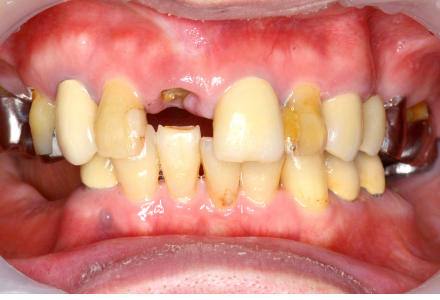

全顎治療症例1

Before

After

- 治療名

- インプラント治療

- 患者さん

- 50代 女性

- 執刀医

- 田中院長

- 治療

内容 - 今回は多数の歯を失われた患者様に対し、インプラント治療を行い、咬合と審美性を回復しました。インプラントによりしっかりと噛める機能を取り戻すと同時に、自然な見た目を再現し口元全体の調和にも配慮しました。患者様から「治療前は人前で口を開けるのも恥ずかしかったのですが、今では安心して笑えるようになりました。食事も快適に楽しめるようになり、田中院長に治療していただき、本当に人生が明るくなりました。」とありがたいお言葉をいただきました。

- 治療期間

- 12ヶ月

- 治療費

- 7,000,000円〜

- リスク

- 歯磨きやメンテナンスが十分に行われない場合、歯ぐきに炎症が起こり、インプラントの安定性に影響が出ることがあります(インプラント周囲炎)。